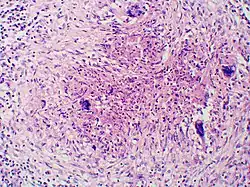

Once suspected, the diagnosis of blastomycosis can usually be confirmed by demonstration of the characteristic broad based budding organisms in sputum or tissues by KOH prep, cytology, or histology.[16] Tissue biopsy of skin or other organs may be required in order to diagnose extra-pulmonary disease. Blastomycosis is histologically associated with granulomatous nodules. Commercially available urine antigen testing appears to be quite sensitive in suggesting the diagnosis in cases where the organism is not readily detected. While culture of the organism remains the definitive diagnostic standard, its slow growing nature can lead to delays in treatment of up to several weeks. However, sometimes blood and sputum cultures may not detect blastomycosis.[17]

Granuloma with early suppuration. Fungal organisms difficult to recognize at this low magnification.